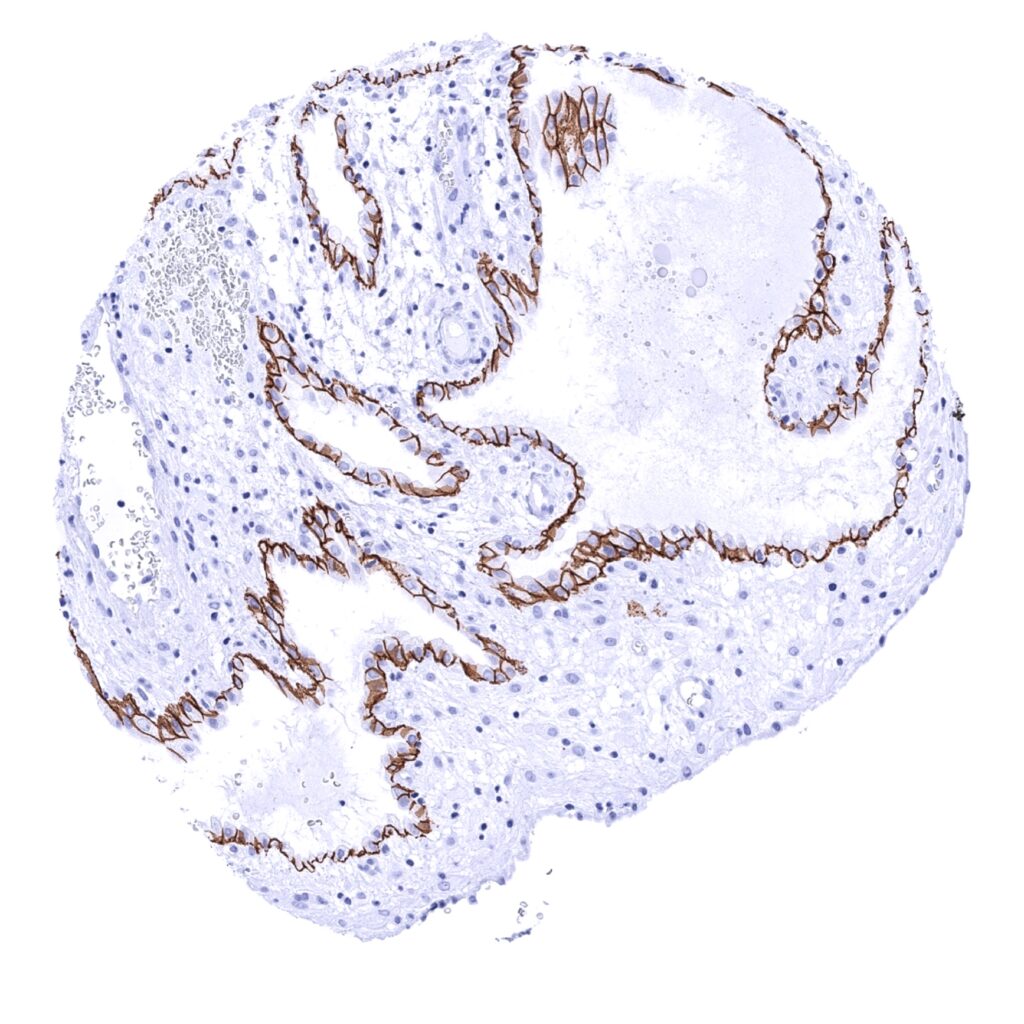

E-Cadherin antibody [MSVA-035R] HistoMAX

Uterus, endocervix